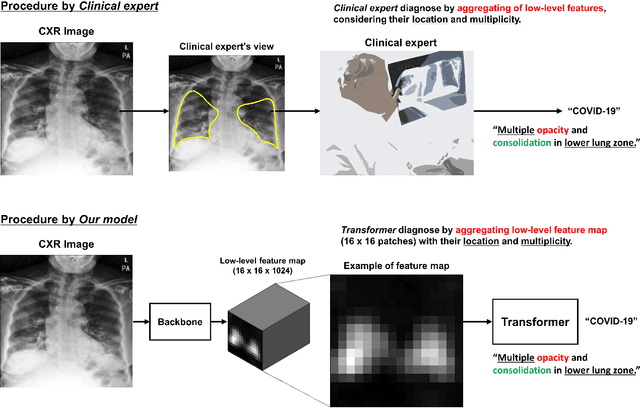

Abstract:Developing a robust algorithm to diagnose and quantify the severity of COVID-19 using Chest X-ray (CXR) requires a large number of well-curated COVID-19 datasets, which is difficult to collect under the global COVID-19 pandemic. On the other hand, CXR data with other findings are abundant. This situation is ideally suited for the Vision Transformer (ViT) architecture, where a lot of unlabeled data can be used through structural modeling by the self-attention mechanism. However, the use of existing ViT is not optimal, since feature embedding through direct patch flattening or ResNet backbone in the standard ViT is not intended for CXR. To address this problem, here we propose a novel Vision Transformer that utilizes low-level CXR feature corpus obtained from a backbone network that extracts common CXR findings. Specifically, the backbone network is first trained with large public datasets to detect common abnormal findings such as consolidation, opacity, edema, etc. Then, the embedded features from the backbone network are used as corpora for a Transformer model for the diagnosis and the severity quantification of COVID-19. We evaluate our model on various external test datasets from totally different institutions to evaluate the generalization capability. The experimental results confirm that our model can achieve the state-of-the-art performance in both diagnosis and severity quantification tasks with superior generalization capability, which are sine qua non of widespread deployment.

Abstract:Under the global COVID-19 crisis, developing robust diagnosis algorithm for COVID-19 using CXR is hampered by the lack of the well-curated COVID-19 data set, although CXR data with other disease are abundant. This situation is suitable for vision transformer architecture that can exploit the abundant unlabeled data using pre-training. However, the direct use of existing vision transformer that uses the corpus generated by the ResNet is not optimal for correct feature embedding. To mitigate this problem, we propose a novel vision Transformer by using the low-level CXR feature corpus that are obtained to extract the abnormal CXR features. Specifically, the backbone network is trained using large public datasets to obtain the abnormal features in routine diagnosis such as consolidation, glass-grass opacity (GGO), etc. Then, the embedded features from the backbone network are used as corpus for vision transformer training. We examine our model on various external test datasets acquired from totally different institutions to assess the generalization ability. Our experiments demonstrate that our method achieved the state-of-art performance and has better generalization capability, which are crucial for a widespread deployment.